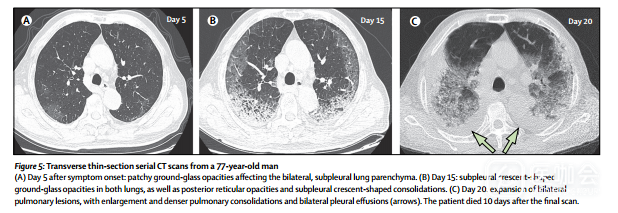

入院后第30天死亡的患者(患者3)是一名77岁的男性,患有高血压,心血管疾病和脑血管疾病。该患者症状发作后第5天CT扫描显示轻度肺炎(图5A),但10天和15天后的两次随访CT扫描显示双侧胸腔积液肺部病变进展迅速(图5B,C)。

图5 患者3横向薄层连续CT扫描影像

在这57例患者中,在所有CT扫描结果中观察到四种演变模式:最初就进展至峰值水平,其后影像学显示有所改善(1型),这种模式在26例(46%)患者中出现(图6),其中24例(92%)患者出院(住院中位时间为25天[IQR 20–27]); 影像学显示持续恶化(2型),包含18名患者(32%)(图5),其中2名(11%)患者死亡(患者2和3); 影像学显示逐步改善(3型),包含8名(14%)患者,其中5名(63%)出院(住院中位时间为19天[IQR 11-25]); 有5名(9%)患者的X线影像学表现没有变化(4型),他们在本研究的截止日期(2月8日)前仍在医院接受治疗。